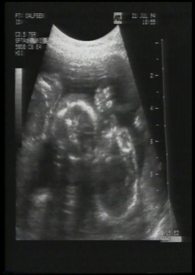

我们总期待着新生命的降临,但却从不知道那来到身旁的,表象为人类的肉块容器中,真的是装着我们所期待的未来吗?

我们是否有权利决定或主导它的一切?